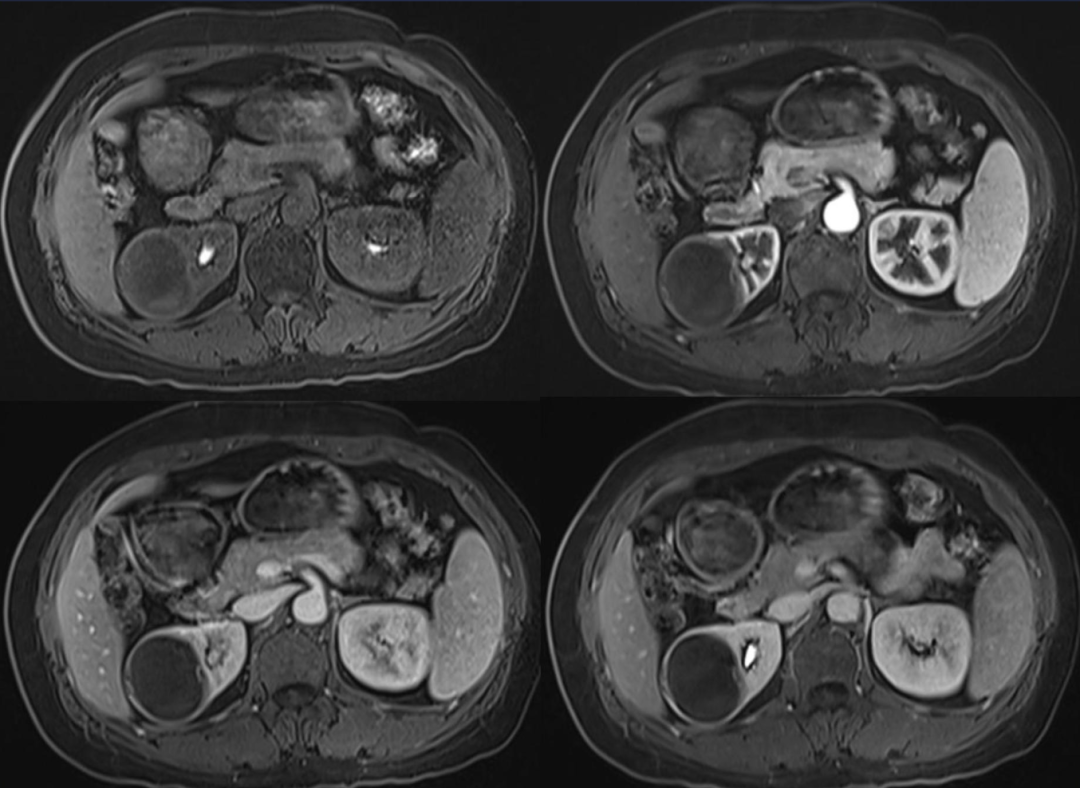

2.肾脓肿:起病急,发热及泌尿系感染症状明显,无结石或钙化。早期炎症期:表现肾实质内略低密度肿块,增强检查可有轻度不规则强化。脓肿成熟期:表现为类圆形均一低密度病变,增强检查病变周边(脓肿壁)呈环状明显强化,中心脓腔低密度无强化,脓肿内可见液气平面和气泡。感染蔓延期:肾周脂肪密度增高;并有脓肿时,表现肾周和肾旁脂肪间隙消失,代之以混杂密度肿块,增强检查表现为规则或不规则单发或多发环状强化。

黄色肉芽肿性肾盂肾炎 | ||

不同程度扩张,边界模糊不清 | ||

脓液,脂质,肉芽肿无对比剂 | ||